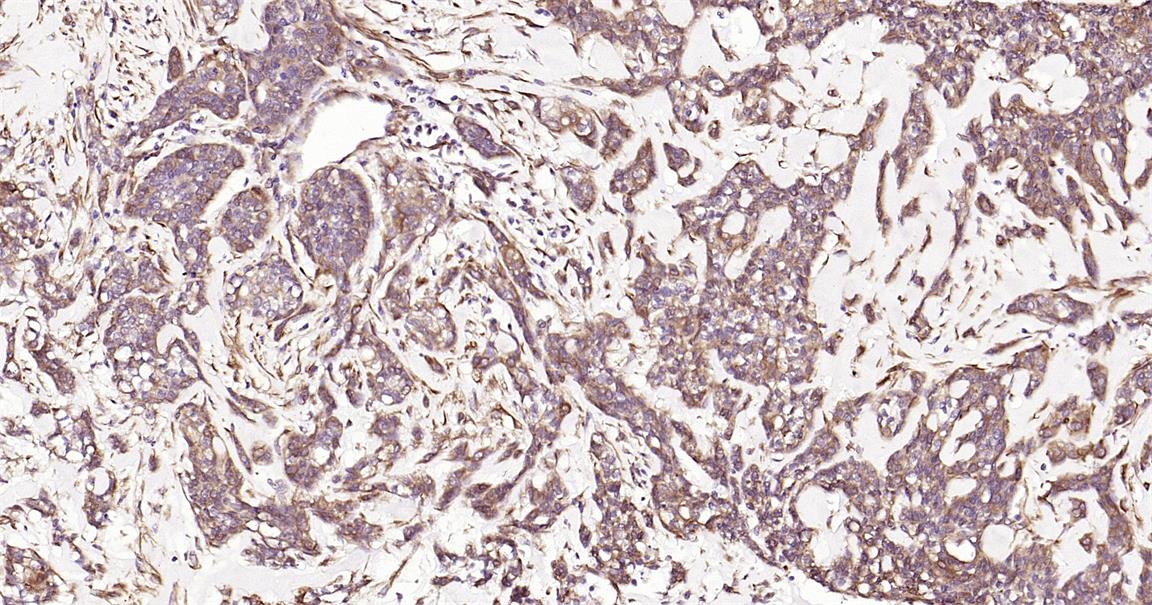

Immunohistochemical analysis of paraffin embedded human gastric cancer tissue slide using IHC0242H (Human HSP47 IHC Kit).

Immunohistochemical analysis of paraffin embedded human breast cancer tissue slide using IHC0242H (Human HSP47 IHC Kit).

Immunohistochemical analysis of paraffin embedded human cervical cancer tissue slide using IHC0242H (Human HSP47 IHC Kit).

Immunohistochemical analysis of paraffin embedded human placenta tissue slide using IHC0242H (Human HSP47 IHC Kit).